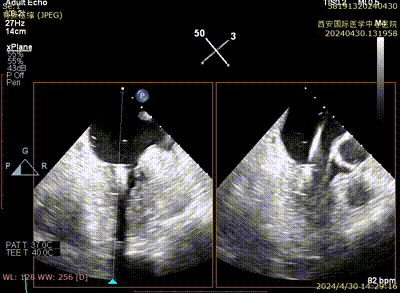

Case 1影像资料

房间隔穿刺

二尖瓣夹系统植入

二尖瓣夹瓣上Trajectory

二尖瓣夹进入左室

二尖瓣夹捕获瓣叶

二尖瓣夹夹闭

术后二尖瓣反流评估

术后结果